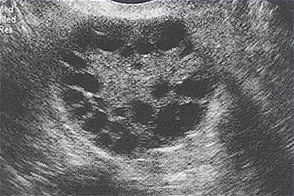

Мультифолликулярный яичник (фото из открытого источника "Интернет")

Важно понимать, что количество фолликулов в яичниках закладывается индивидуально. В течение жизни мы эти самые фолликулы постепенно «расходуем», двигаясь к менопаузальному состоянию. Обычно при проведении ультразвуковой диагностики врач УЗИ подсчитывает сколько фолликулов он видит в одном яичнике. Их количество может быть от 6 до 10 штук в одном ультразвуковом срезе. Но, бывает, что их количество может достигать и 15. Когда врач УЗ- диагностики видит их от 12 в поле зрения одного яичника, то он выносит заключение – мультифолликулярные яичники. Кстати, иногда, так бывает, что такой яичник только один.